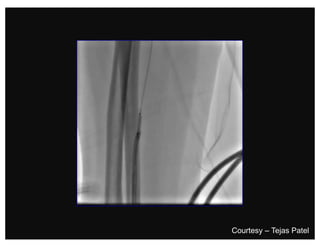

Traversing a radial loop

Brachial Tortuosity

Courtesy – Tejas Patel